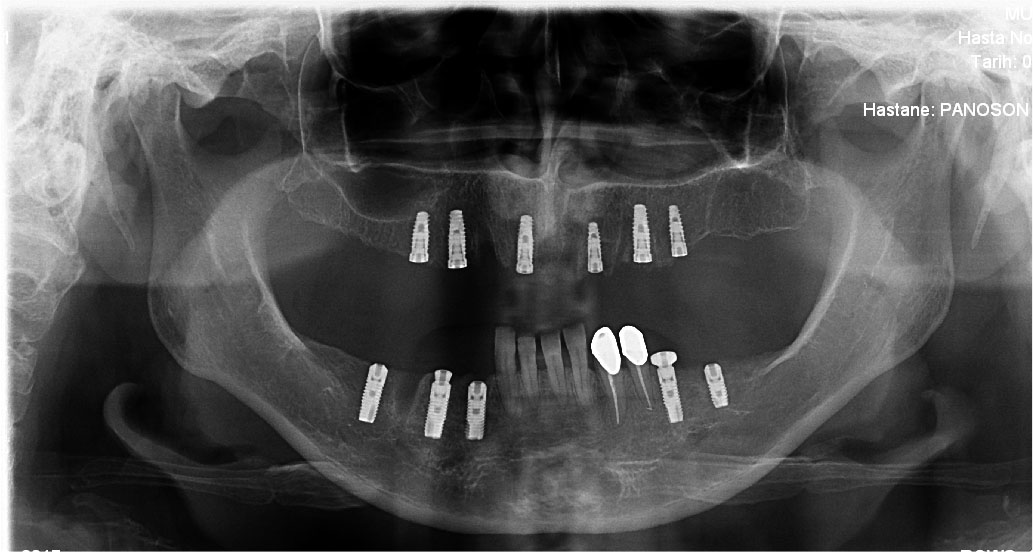

Ýmplant

Oral Diagnoz ve Radyoloji